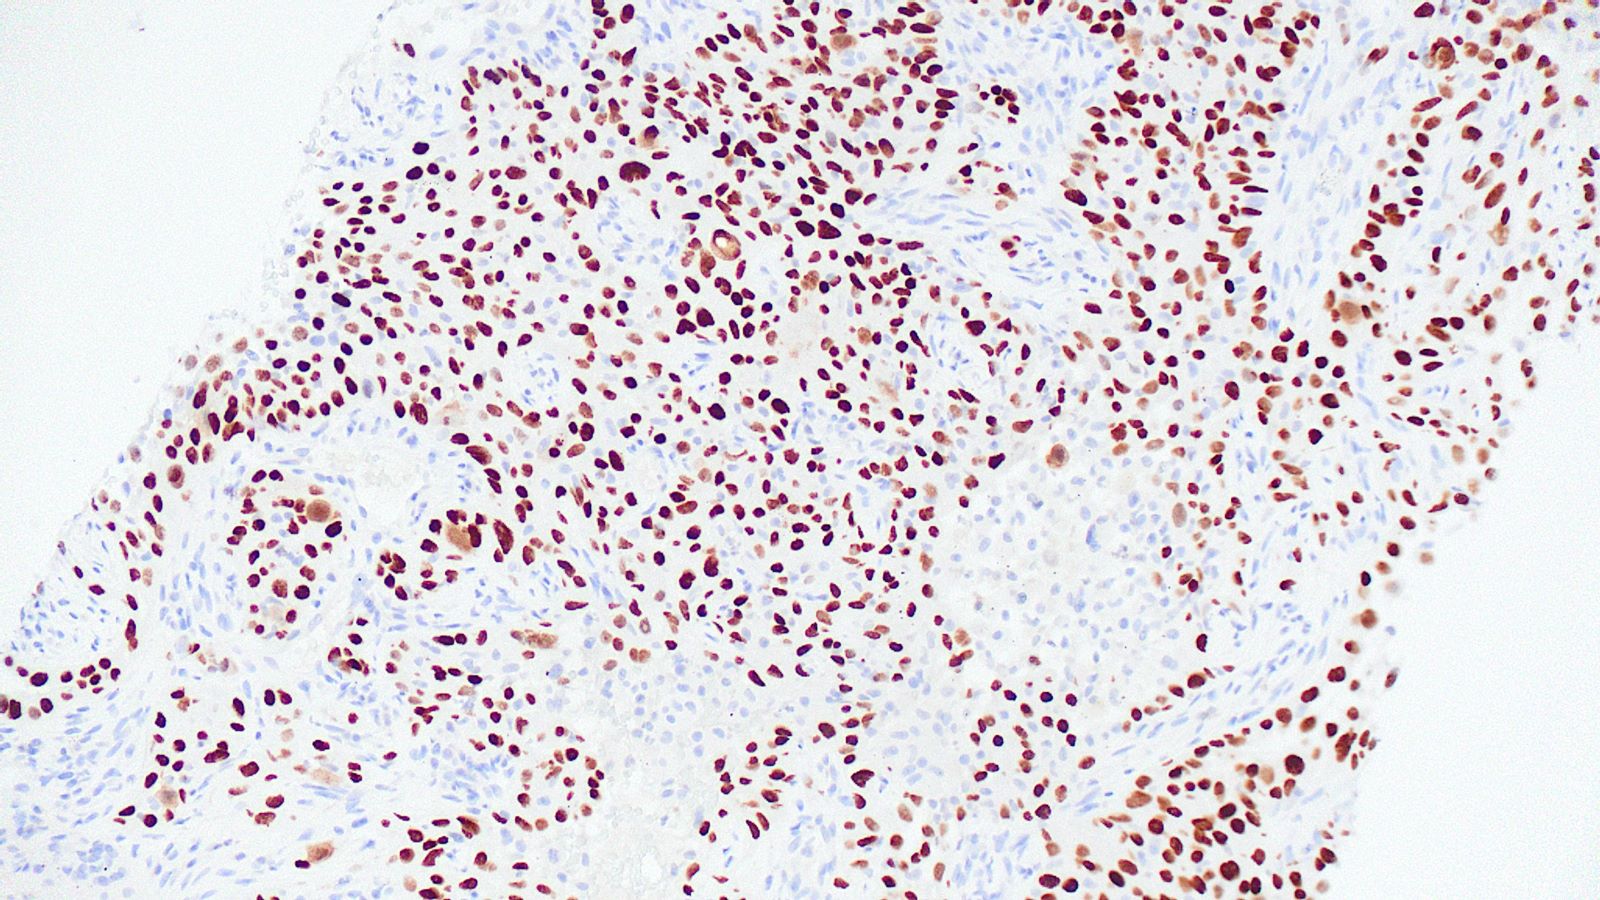

Board review style question #3

A 75 year old man with a 100 pack year smoking history presents with hemoptysis and is found to have a hilar mass and lymphadenopathy. Biopsy of one of the lymph nodes reveals the proliferation seen in the above images. Mitotic activity is approximately 35 mitoses per 2 mm2 and necrosis is present. Immunophenotyping is attempted; however, the block was inadvertently exhausted and stains are not available. What is the best diagnosis that can be rendered?

Board review style answer #3

E. Small cell carcinoma. Small cell carcinoma remains a morphologic diagnosis and does not require immunophenotyping for confirmation. The clinical history and description of the malignant cells are consistent with a diagnosis of small cell carcinoma. Immunophenotyping, including the use of Ki67, is most useful in cases with more ambiguous morphologic features or in crushed biopsies where morphologic features are obscured.